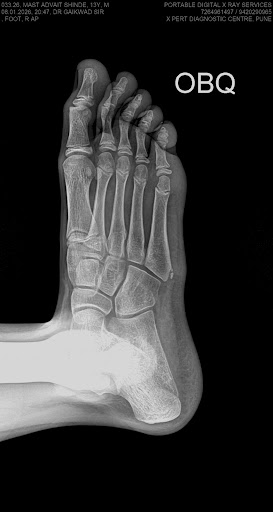

X-ray

Digital Xray

Advanced digital xray

Gallery